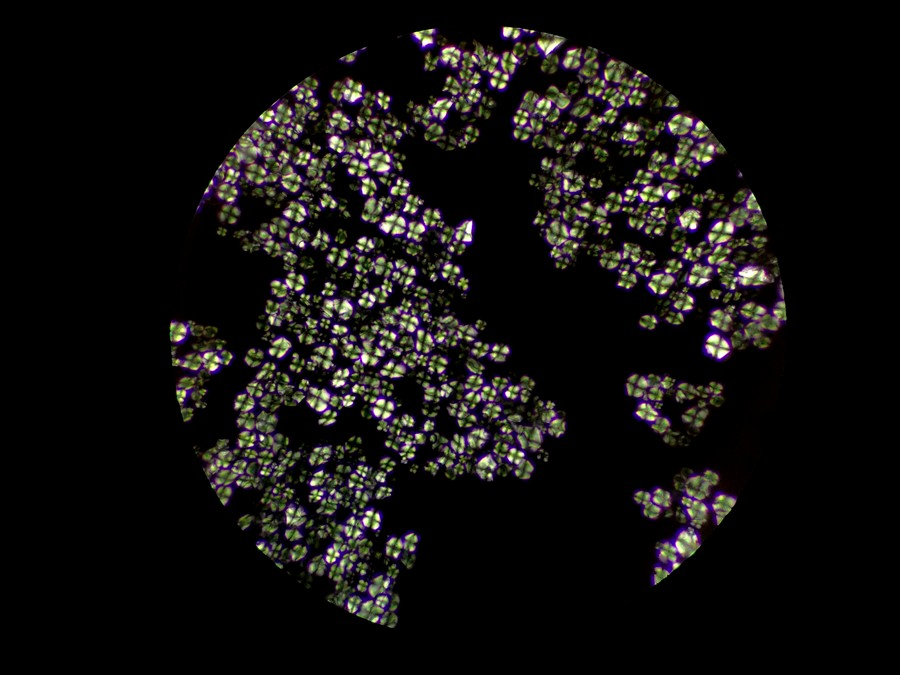

偏光下的中藥顆粒

偏光觀察是對結晶物質的形態進行觀察和測量的一種技術,在生物顯微鏡ML31基礎上加入偏光附件,即可升級為簡易偏光顯微鏡ML31-P,正交偏光下可以看到顆粒出現了偏光反應,形成以粒心為中心的黑色“十”字外觀,這是淀粉粒的典型特征。

在其他視野中,我們也看到了一些其他偏光反應,可能是草酸鈣簇晶之類成分,也可能是玻片或者水中的雜質。

中藥顆粒在鏡下可見的成分是淀粉輔料,可在偏光觀察下形成偏光十字,而其有效成分是提取濃縮出來的中藥分子,無法用顯微鏡觀察,需要通過液相色譜等方法才能檢測。